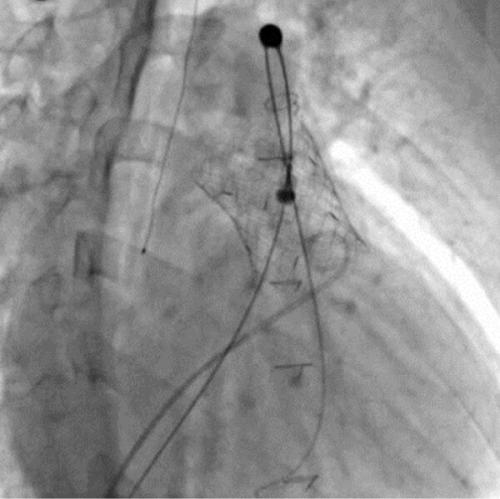

¼­¿ï´ëº´¿ø ¼Ò¾Æ½ÉÀå¼¾ÅÍ ÀÇ·áÁøÀÌ °æÇÇÀû Æóµ¿¸ÆÆÇ¸· ġȯ¼ú(PPVI)À» ½ÃÇàÇϰí ÀÖ´Ù.(»çÁøÁ¦°ø=¼­¿ï´ëº´¿ø)

°æÇÇÀû Æóµ¿¸ÆÆÇ¸· ġȯ¼úÀº °¡½¿À» ¿­Áö ¾Ê°í Çã¹÷Áö Á¤¸ÆÀ» ÅëÇØ Ä«Å×ÅÍ·Î Àΰø ÆÇ¸·À» »ðÀÔÇÏ´Â ÃÖ¼Ò Ä§½À Ä¡·á´Ù. ¼±Ãµ¼º ½ÉÀ庴 ȯÀÚ °¡¿îµ¥ Æóµ¿¸ÆÆÇ¸· ±â´ÉÀÌ ÀúÇÏµÈ °æ¿ì ½ÃÇàµÇ¸ç, ¹Ýº¹ÀûÀÎ °³È䡤°³½É¼ö¼úÀ» ´ë½ÅÇϰųª ½ÃÁ¡À» ´ÊÃâ ¼ö ÀÖ´Â Ä¡·á ¹æ¹ýÀ¸·Î Ȱ¿ëµÇ°í ÀÖ´Ù.

°æÇÇÀû Æóµ¿¸ÆÆÇ¸· ġȯ¼ú(PPVI) ½Ã¼ú Àå¸é(»çÁøÁ¦°ø=¼­¿ï´ëº´¿ø)